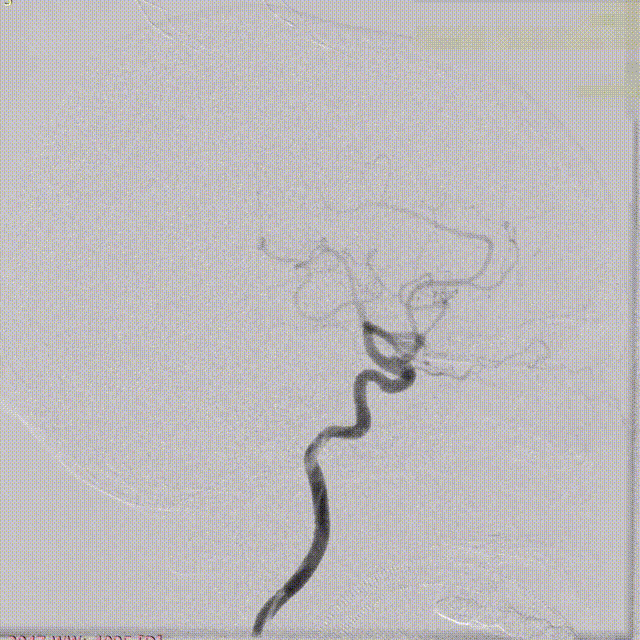

盖延廷教授病例分享一:左侧颈内动脉多发动脉瘤

患者:女性,55岁。

主诉:头疼,检查发现动脉瘤8月余。

入院查体:颅内多发动脉瘤。

术前诊断:

左侧颈内动脉:

远端锚定点脉前起始近端;近端锚定点海绵窦段。

载瘤动脉远端血管直径:3.23 mm

载瘤动脉近端血管直径:4.17 mm

选用4.25mm*25mm 强易达(Choydar)密网支架。

支架及支架微导管到位。

支架头端打开。

支架远端打开造影。

等张释放,支架中段打开至50%释放标记点。

支架中段打开造影。

支架近端打开,完全释放。

支架完全释放造影。

术后即刻造影。

术后重建。